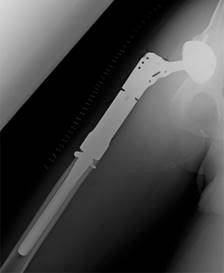

La artroplastía total se realizó con una prótesis modular del sistema Zimmer Biomet (Warsaw, IN, USA) (Figura 4) con una copa acetabular no cementada OsseoTi Limited Hole de 4 orificios de 54 mm fijada con dos tornillos de 6.5 × 20 mm, liner de CoCr G7 de doble movilidad de 44 mm, núcleo de polietileno infundido con vitamina E1 (antioxidante) de 28 × 44 mm, cabeza de CoCr de 28 mm +6, segmento proximal Finn de 7 cm, segmento diafisario de 9 cm, vástago no cementado de 150 × 14.5 mm y colocación de cerclaje Cable Grip System de 1.8 mm, el cual fue colocado a manera de reforzamiento previo a la impactación del vástago femoral, ya que posterior a la osteotomía femoral, durante la regularización de los bordes, se identificó sutil fragmentación de la cortical anteromedial del fémur, así que, de forma profiláctica, se decidió utilizar un cerclaje previo a la impactación del vástago femoral (Figura 5). La herida se cubrió con un parche con sistema de presión negativa que favoreciera el control necesario del exudado de la herida con el objetivo de evitar la formación de hematomas y/o seromas. Durante el período postoperatorio, el paciente permaneció cuatro días hospitalizado, restringiéndose el apoyo durante los primeros dos días, comenzó con sesiones de medicina física y rehabilitación, iniciando con apoyo parcial el día tres de su postoperatorio. El paciente fue dado de alta clínica y hemodinámicamente estable, sin la necesidad de transfusión de hemoderivados.

Figura 4: Prótesis modular, Zimmer Biomet (Warsaw, IN, USA). A) Sistema modular femoral (segmento proximal de 7 cm, segmento diafisario de 9 cm y vástago no cementado de 150 × 14.5 mm). B) Cabeza protésica de CoCr de 28 mm en núcleo de polietileno vitaminado de 28 × 44 mm (vitamina E1 antioxidante) C) Liner de CoCr de doble movilidad de 44 mm.

Figura 5: Radiografía anteroposterior de cadera derecha que evidencia resección de fémur proximal, así como colocación de prótesis total modular de cadera y colocación de cerclaje de reforzamiento.